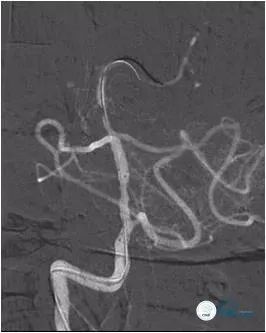

将Transend微导丝(0.014″,300cm)通过狭窄,放置在左小脑上动脉,沿微导丝送入Gateway球囊(2.0mm×15.0mm)于狭窄处预扩张(图12)。

图12

撤出球囊导管,沿Transend微导丝送入Wingspan自膨式支架(3.0 mm×20.0mm),释放后造影示支架贴壁良好,前向血流TICI 3级(图13,14)。

图13

图14